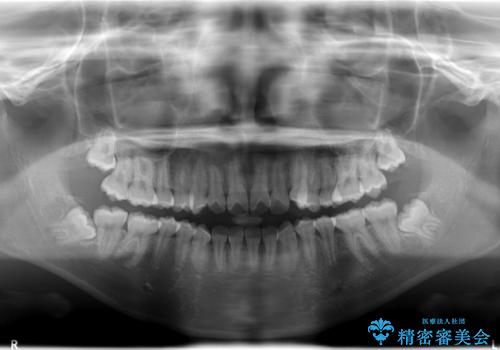

ハーフリンガル 半分裏側矯正による上下前突の抜歯矯正治療

- 上下左右4本の第1小臼歯を抜歯する、抜歯矯正を計画した。

抜歯矯正により前歯の位置が後ろに下がり、わずかではありますが、口元に改善がみられ、歯並びもきれいに整いました。